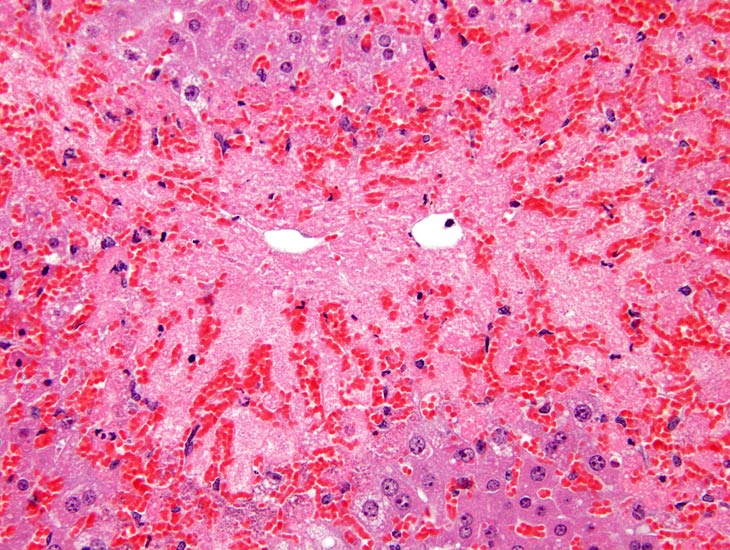

This is an example of centrilobular hepatocellular necrosis with associated hemorrhage sometimes referred to as hemorrhagic necrosis.